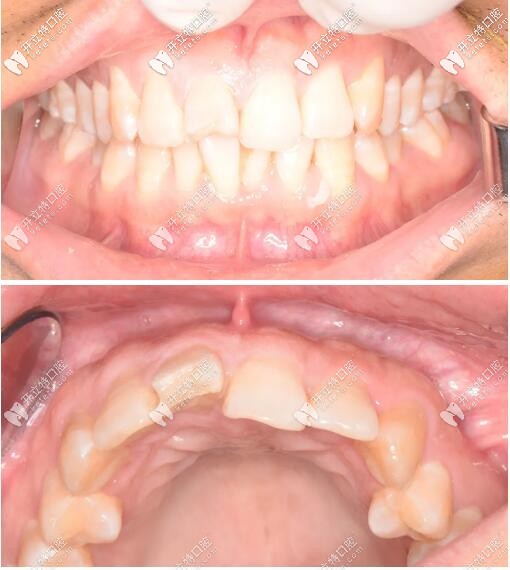

口內(nèi)檢查

被磕的11號(hào)牙(門牙)切端1/3折斷,并見不規(guī)則縱向裂紋;

牙齦色粉、質(zhì)韌,無明顯紅腫,牙齦乳頭充盈。